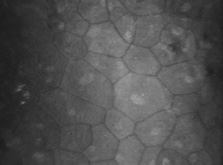

skin. Am J PathoI 116:417, 1984 36. Newsome DA, Foidart JM, Hassell JH, et al: Detection of specific collagen types for normal and keratoconus corneas. Invest Ophthalmol Vis Sci 20:738, 1981 37. Nakayasu K, Tanaka M, Konomi H, et al: Distribution of types I, II, III, IV, and V collagen in normal and keratoconus

corneas. Ophthalmic Res 18:1, 1986 38. Kolega J, Manabe M, Sun T-T: Basement membrane heterogeneity and variation in corneal epithelial differentiation. Differentiation 42:54, 1989 39. Cleutjens JP, Havenith MG, Kasper M, et al: Absence of type IV collagen in the centre of the corneal epithelial basement